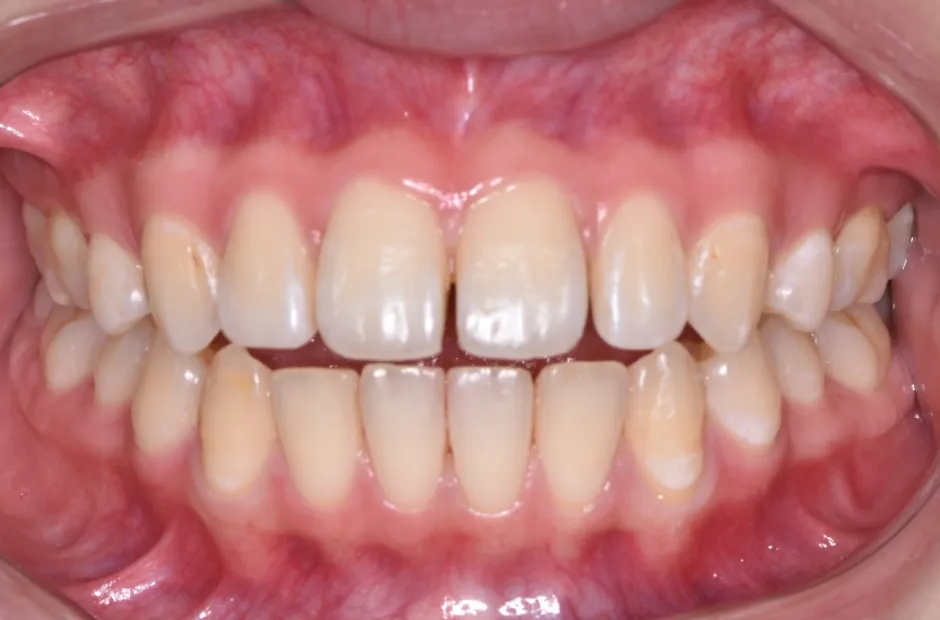

空隙歯列・すきっ歯

| 診断名・主訴 | 空隙歯列・すきっ歯 |

|---|---|

| 年齢・性別 | 49歳・女性 |

| 治療期間・回数 | 1年半 |

| 治療に用いた主な装置 | アクアシステム |

| 抜歯部位 | なし |

| 治療費 | 60万円(税抜) |

| リスク・副作用 | 装置による違和感・疼痛・歯肉退縮・歯根吸収・虫歯のリスクなど |

治療前

治療後